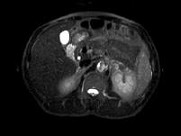

- 单项选择题男,52岁, 下肢无力伴多饮多尿2年余,实验室检查: 低血钾,血醛固酮水平及24h尿醛固酮定量超过正常值, MRI检查如图所示,应诊断为 ( )

A、左肾上腺囊肿

B、左肾上腺腺瘤

C、左肾上腺嗜铬细胞瘤

D、左肾上腺髓脂瘤

E、左肾上腺转移癌